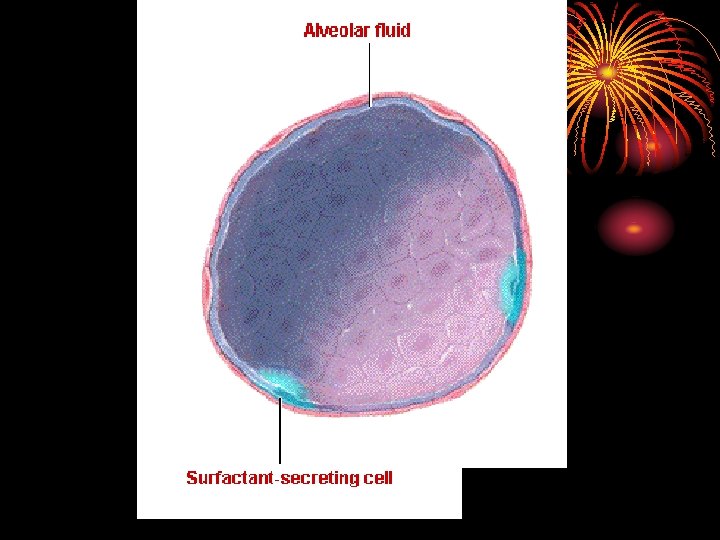

• area from 2. 5 cm 2 (trachea) to 11800 cm 2 in alveoli ? Air velocity. • 300 million alveoli, 70 m 2. • Alveoli lined by type 1 cells ( flat lining ) and type 11 cells ( granular pneumocytes secrete surfuctant ). • Pleura. • Respiratory muscles.

Surfactant • Lipid surface tension lowering agent. • Produced by type II alveolar epithelial cell. • Composed of phospholipids, neutral lipids, proteins and CHO. • Functions: 1. Lower surface tension in alveoli. 2. Helps to prevent pulmonary edema.

• Maturation of surfactant is accelerated by glucocorticoid (cortisol). • Surfactant decreases in smokers. • Cardiac surgery with interruption of pulm circulation, pulm, artery occlusion, main bronchus occlusion and long term 100% 02 can decrease surfactant.

• Surfactant deficiency can cause infant respiratory distress syndrome (IRDS, hyaline membrane disease) in premature babies. • Surfactant (Synthetic and bovine) can be given by inhalation.